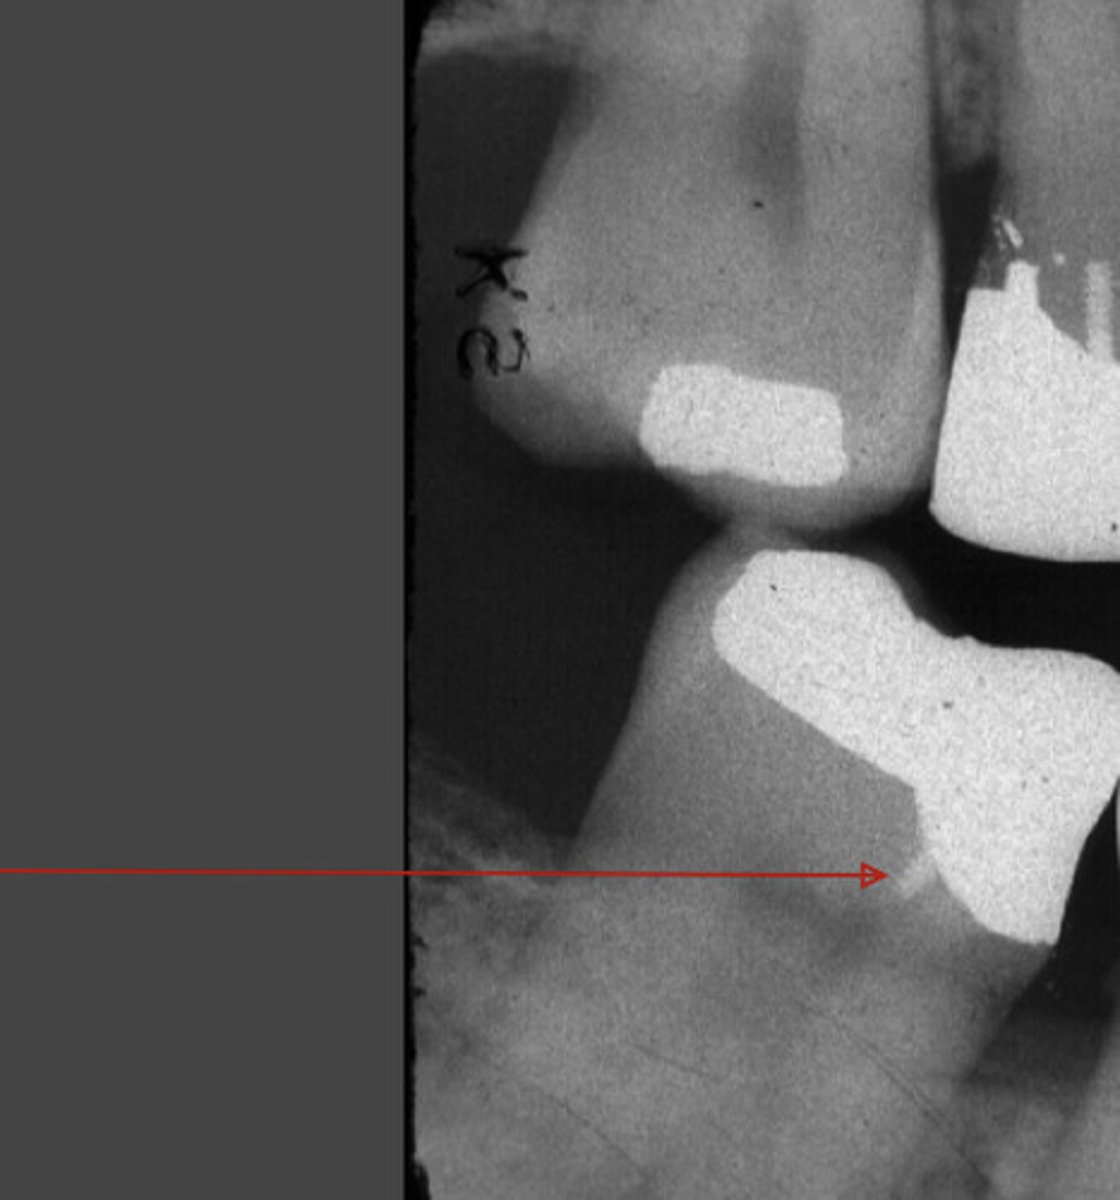

retention pin

base